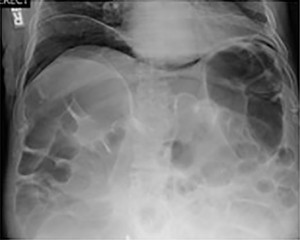

The patient is a 72-year-old male with a symptomatic history of severe chronic pain in bilateral buttocks and lumbosacral regions as well as a prominent L2 spinous process. His past medical history included hypertension, hyperlipidemia, gastroesophageal reflux disease, nephrolithiasis, deep venous thrombosis, and severe postoperative constipation after prior surgery, which was successfully treated with conservative management. His surgical history included bilateral inguinal hernia repair, removal of nephrolithiasis, and multiple posterior spinal surgeries resulting in fusion from L2-L5. He had continued symptoms of lumbosacral spondylosis with failure of nonoperative management including physical therapy, injections, and pharmaceutical therapy. Radiographic (Figure 1) and MRI findings were consistent with degenerative disc disease of L5-S1 and evidence of successful fusion L2-L5.